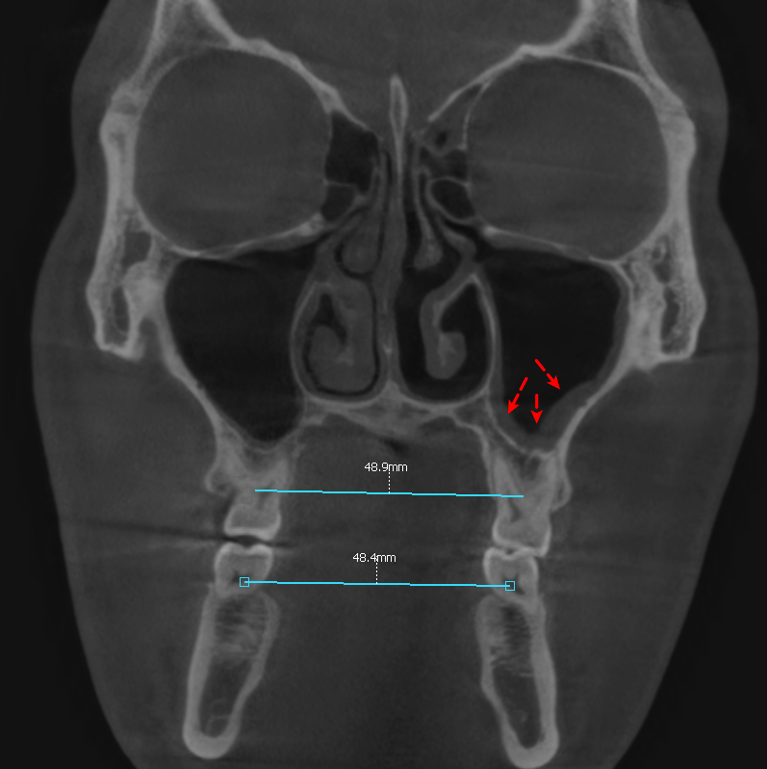

23.08.17

더불어, 위 어금니 간의 폭경과

아래 어금니 간의 폭경의 비율은 정상으로

확인되었으며,

왼쪽 비강에 상악동염이 관찰되었습니다.